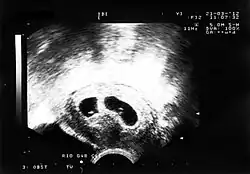

Zwillinge (lateinisch gemini) sind zwei Kinder einer Mutter, die in derselben Schwangerschaft herangewachsen sind und meistens auch im gleichen Geburtsvorgang zur Welt kommen.[1][2][3][4]

Bei der seltenen Überschwängerung wachsen ebenfalls zwei oder mehr Kinder intrauterin gemeinsam heran. In der Zwillingsforschung werden Paare zweieiiger (dizygotischer) und eineiiger (monozygotischer) Zwillinge verglichen.